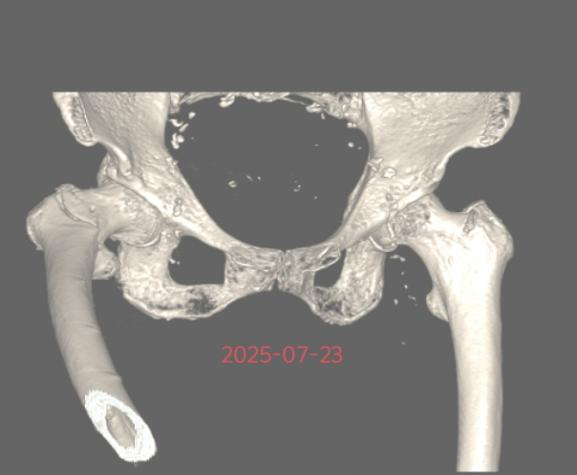

近期,85岁李奶奶,因摔倒致右股骨粗隆间粉碎性骨折,来我院就诊。

患者高龄,并发高血压、冠心病及肺部基础疾病,我院骨科团队迅速联合内科主任、麻醉科医师进行多学科会诊,评估病情,最终确定在腰麻下行右股骨粗隆间骨折闭合复位髓内钉内固定手术方案。安庆市第一人民医院骨科何流教授率领王亮主治医师通过 3 个小切口完成骨折复位与固定,手术顺利,术后恢复良好,术后5天李奶奶可以翻身自行坐起,目前在助行器辅助下部分负重行走。